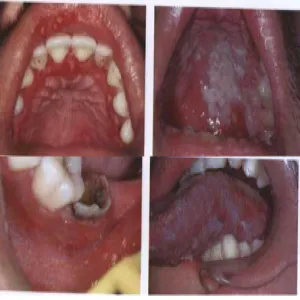

Grzybica jamy ustnej

Grzybica w jamie ustnej